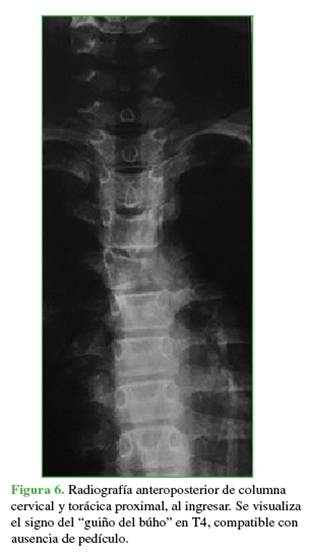

En la radiografía anteroposterior de ingreso, se identificó la ausencia de una imagen pedicular en la vértebra afectada, signo conocido como “guiño del búho” (Figura 6).12

Keywords: Aneurysmal bone cyst; thoracic spine; neurological compromise; embolization; spinal surgery; tumor.